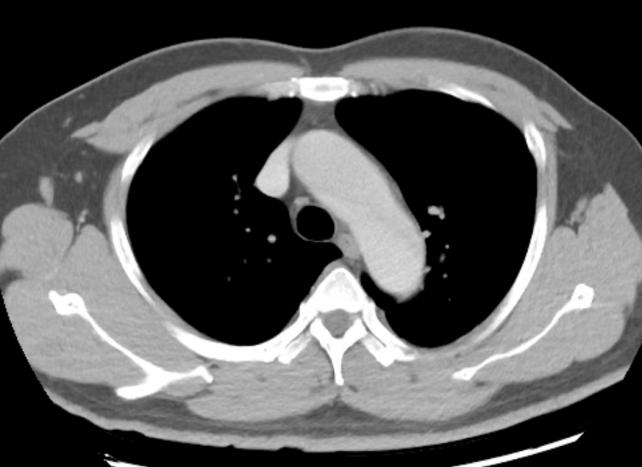

灌注不足 主动脉弓CT值过低